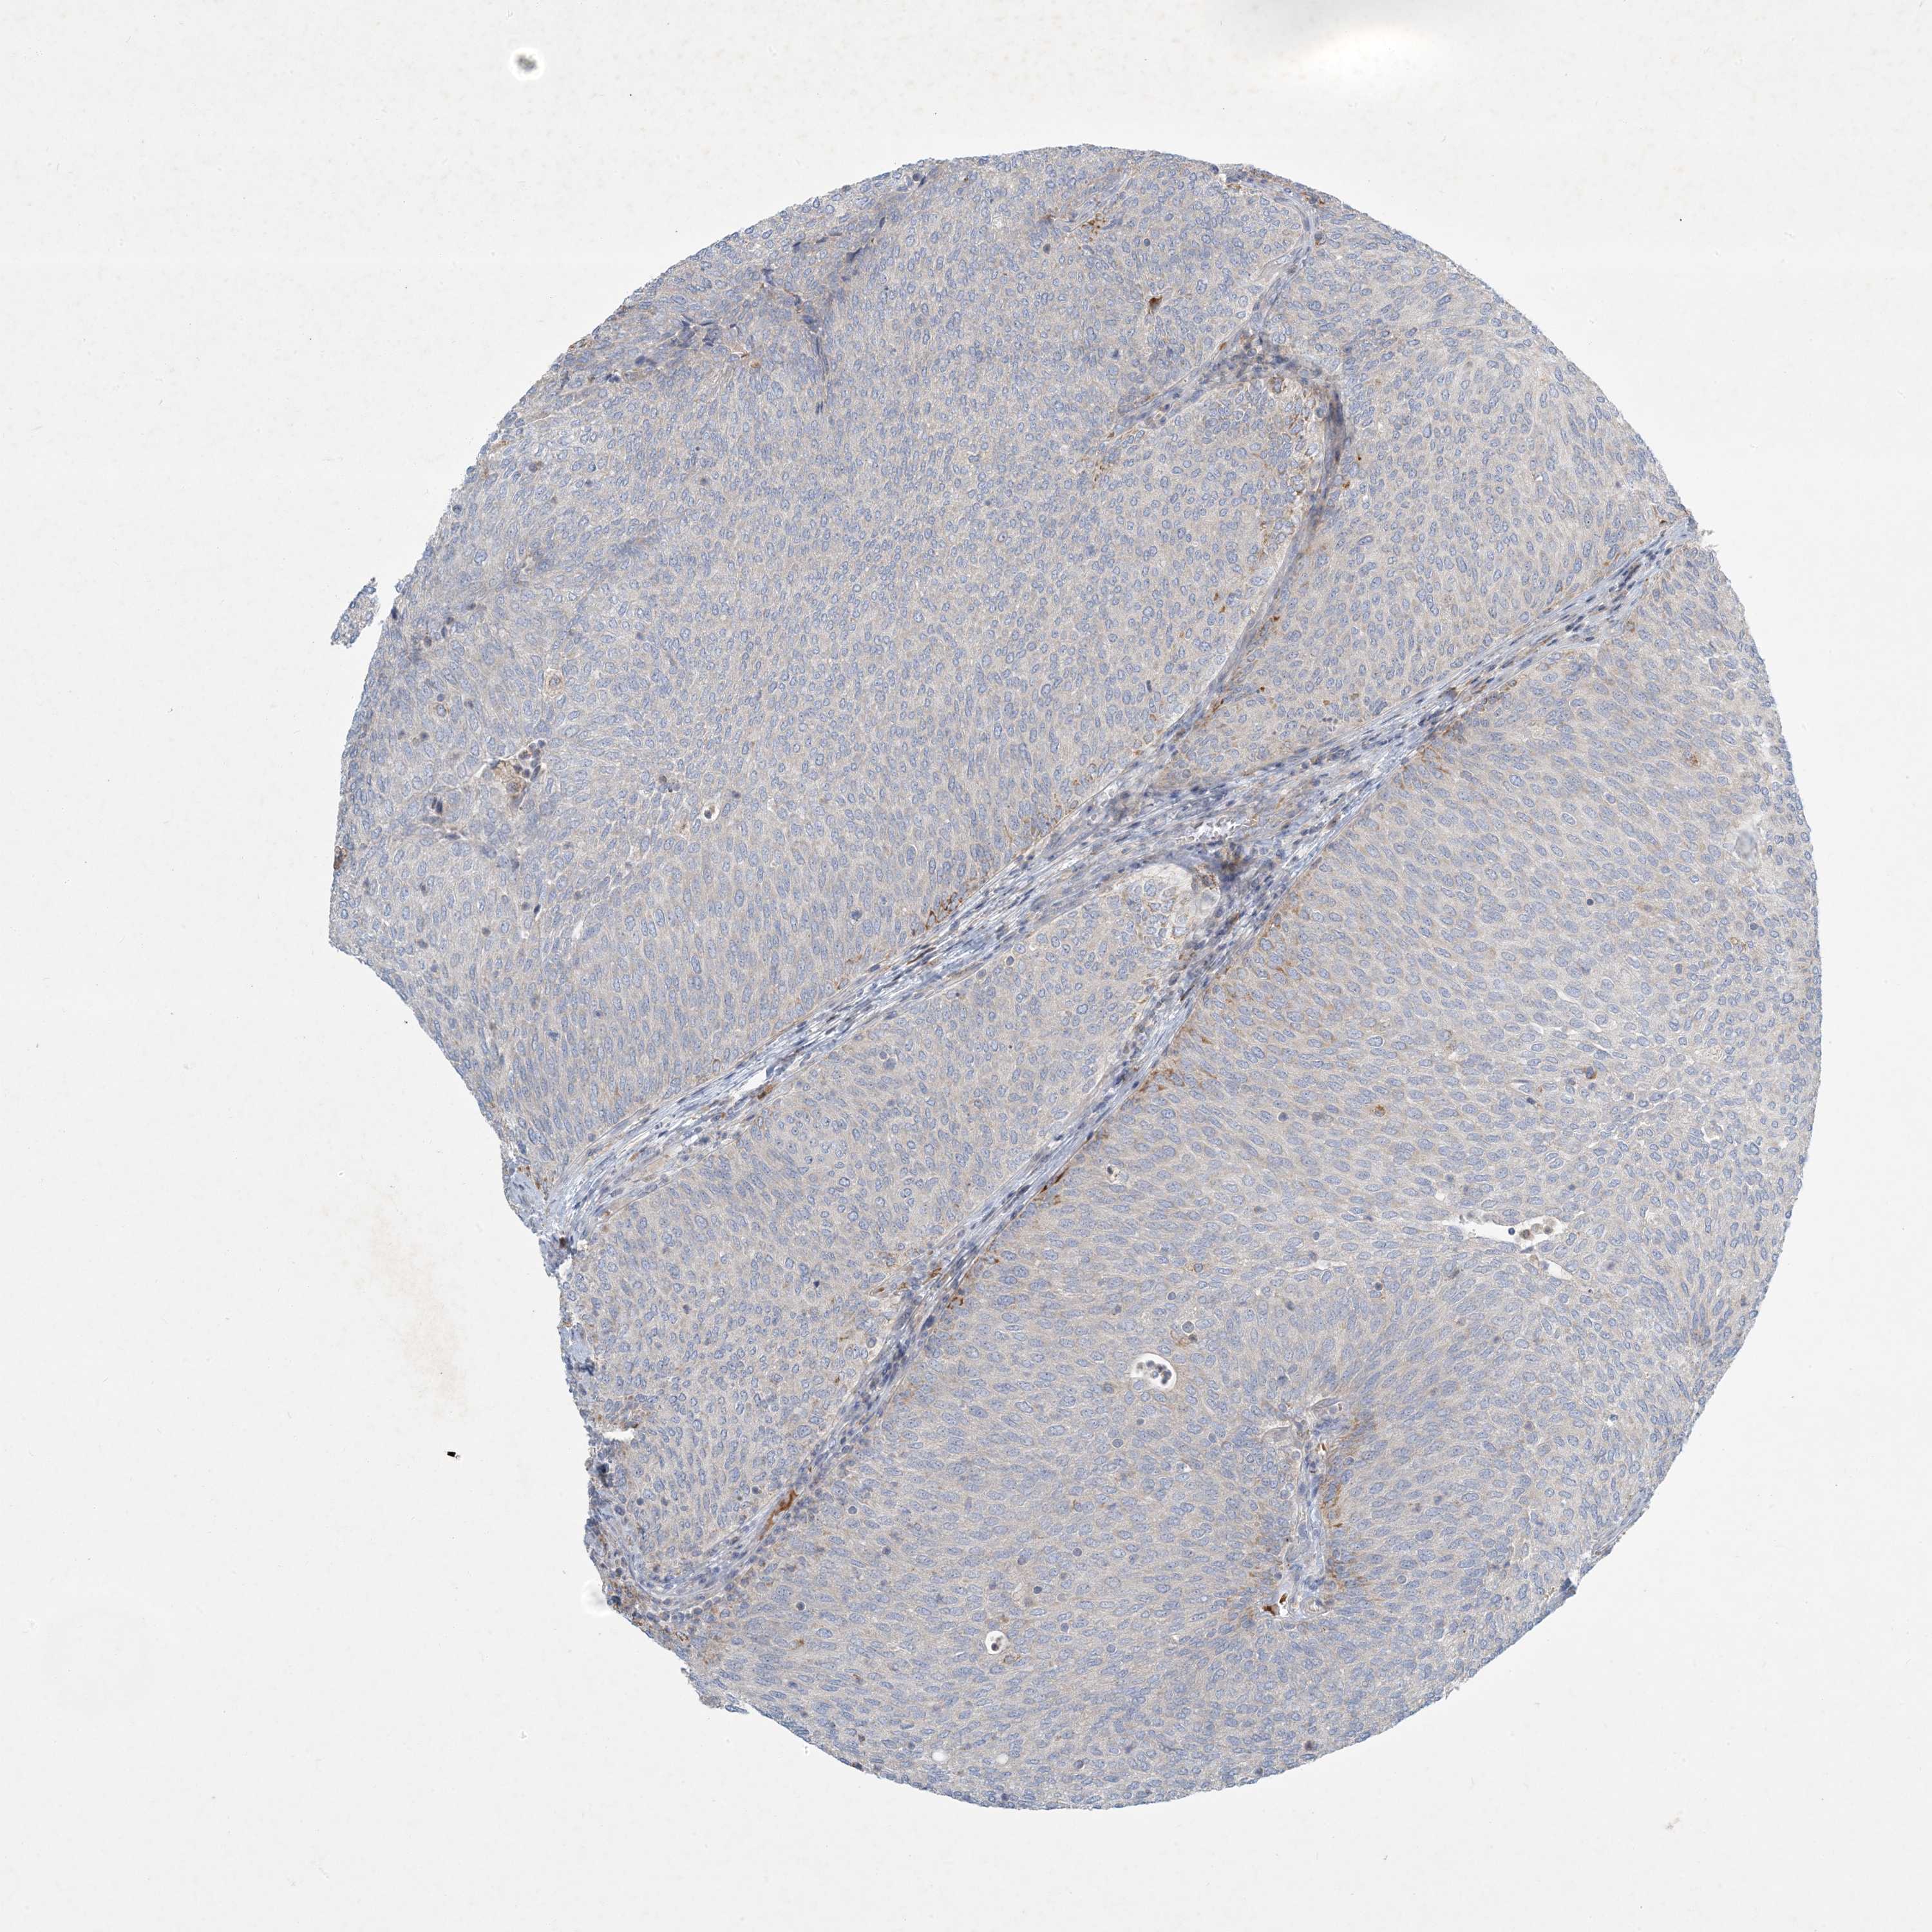

UROTHELIAL CANCER - Protein expressioni

A mouse-over function shows sample information and annotation data. Click on an image to view it in a full screen mode. Samples can be filtered based on level of antibody staining by selecting one or several of the following categories: high, medium, low and not detected. The assay and annotation is described here.

Antibody stainingi

Antibody staining in the annotated cell types in the current human tissue is reported as not detected, low, medium, or high, based on conventional immunohistochemistry profiling in selected tissues. This score is based on the combination of the staining intensity and fraction of stained cells.

Each image is clickable and will lead to virtual microscopy that enables deeper exploration of all samples and also displays staining intensity scores, fraction scores and subcellular localization as well as patient and tissue information for each sample.

Antibody HPA029143

Antibody CAB034164

Urothelial carcinoma, Low grade

Urothelial carcinoma, High grade